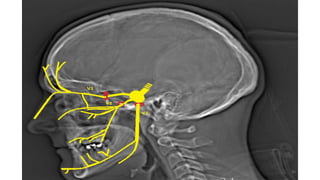

Origin of cranial nerves

1. Magnetic resonance imaging (MRI) is the gold standard

technique in the study of the cranial nerves

2. Steady-state free procession (SSFP) images are the best

sequences for the visualization of the cisternal segments

showing dark cranial nerves against a background of bright

cerebrospinal fluid (CSF)